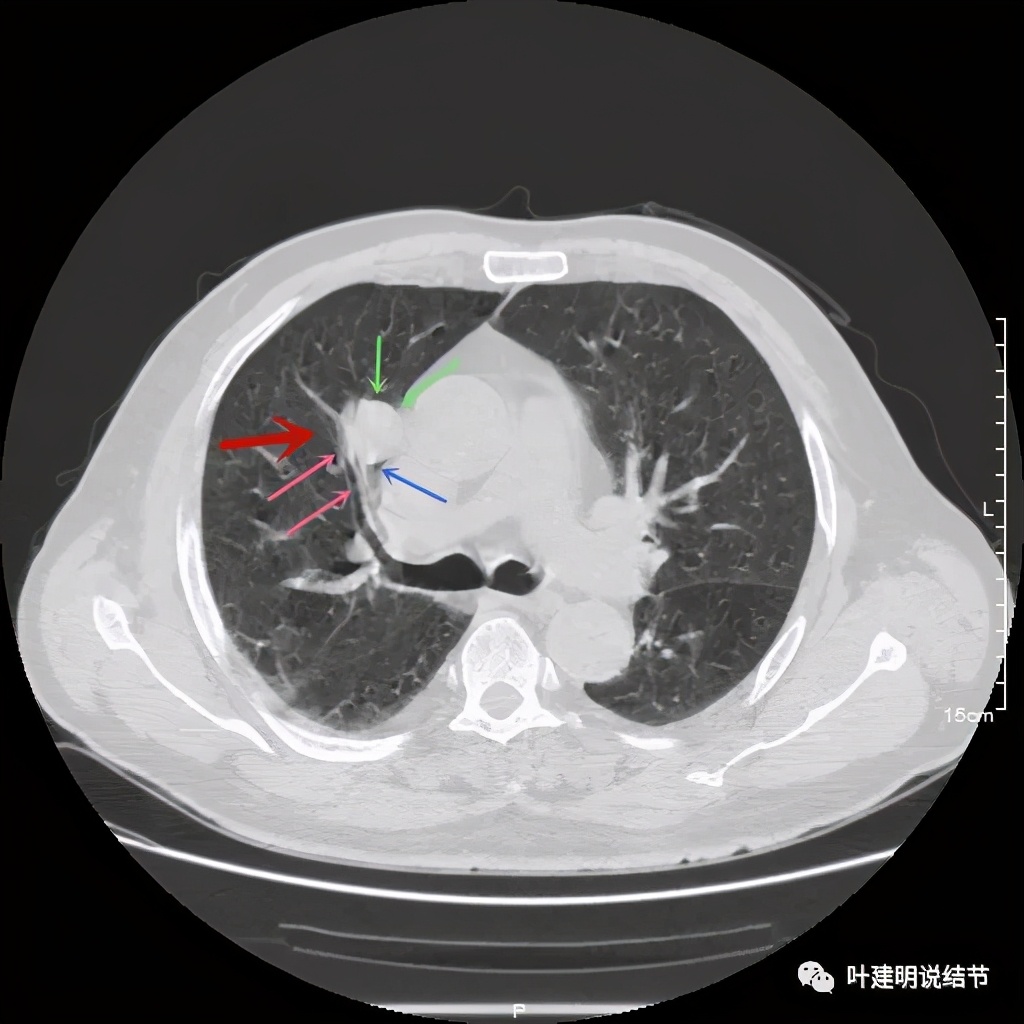

上图也示病灶密度不均,但边缘过于光滑(绿色);支气管似有截断(粉色);局部有点状钙化(蓝色)

上图示病灶边缘过于光滑(绿色);局部有点状钙化(蓝色)

上图示病灶边缘过于光滑(绿色);血管贴边(桔色);